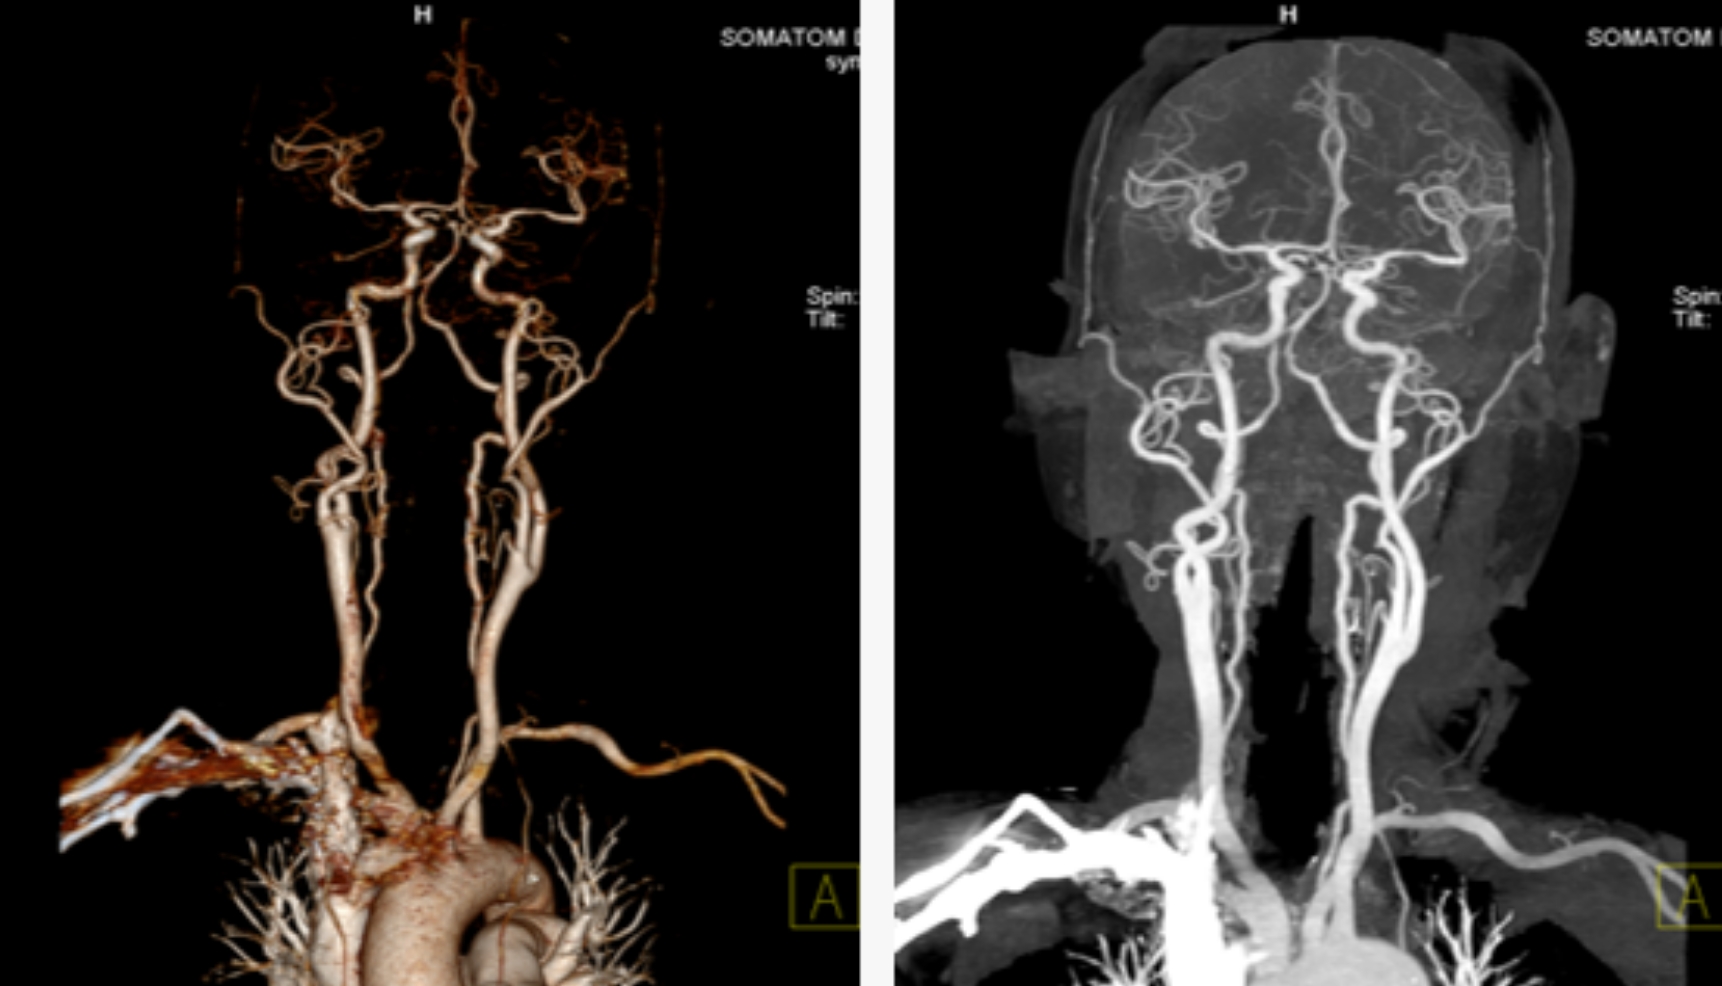

本次引進(jìn)的全新64排128層人工智能螺旋CT具有檢查更加精細(xì)、圖像更加清晰、掃描速度快和輻射劑量小等多種優(yōu)點(diǎn)。除了可進(jìn)行常規(guī)CT檢查、普通增強(qiáng)CT檢查外,還可對(duì)全身大血管、腦血管、心臟血管進(jìn)行檢查;強(qiáng)大的三維重建功能可發(fā)現(xiàn)普通DR、常規(guī)CT所難確診的病變。

用該設(shè)備做心血管系統(tǒng)檢查,能得到對(duì)比度極佳的血管圖像。大大提高了診療的精準(zhǔn)度及工作效率,有利于醫(yī)生及早發(fā)現(xiàn)微小病灶。

該設(shè)備,可以在短時(shí)間完成對(duì)冠狀動(dòng)脈缺血、肺栓塞、主動(dòng)脈瘤的一站式檢查,也可在在短時(shí)間完成對(duì)頭部血管、頸部血管、腦實(shí)質(zhì)血液灌注的一站式檢查,為腦卒中和急性胸痛患者的早期診斷和治療能力贏得黃金時(shí)間。